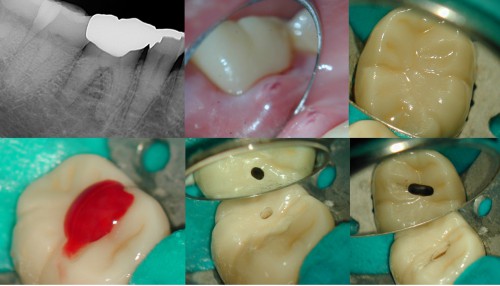

Lower Molar w/IP prior to getting a crown

This patient was referred after she develop cold sensitivity while she was in a temporary […]